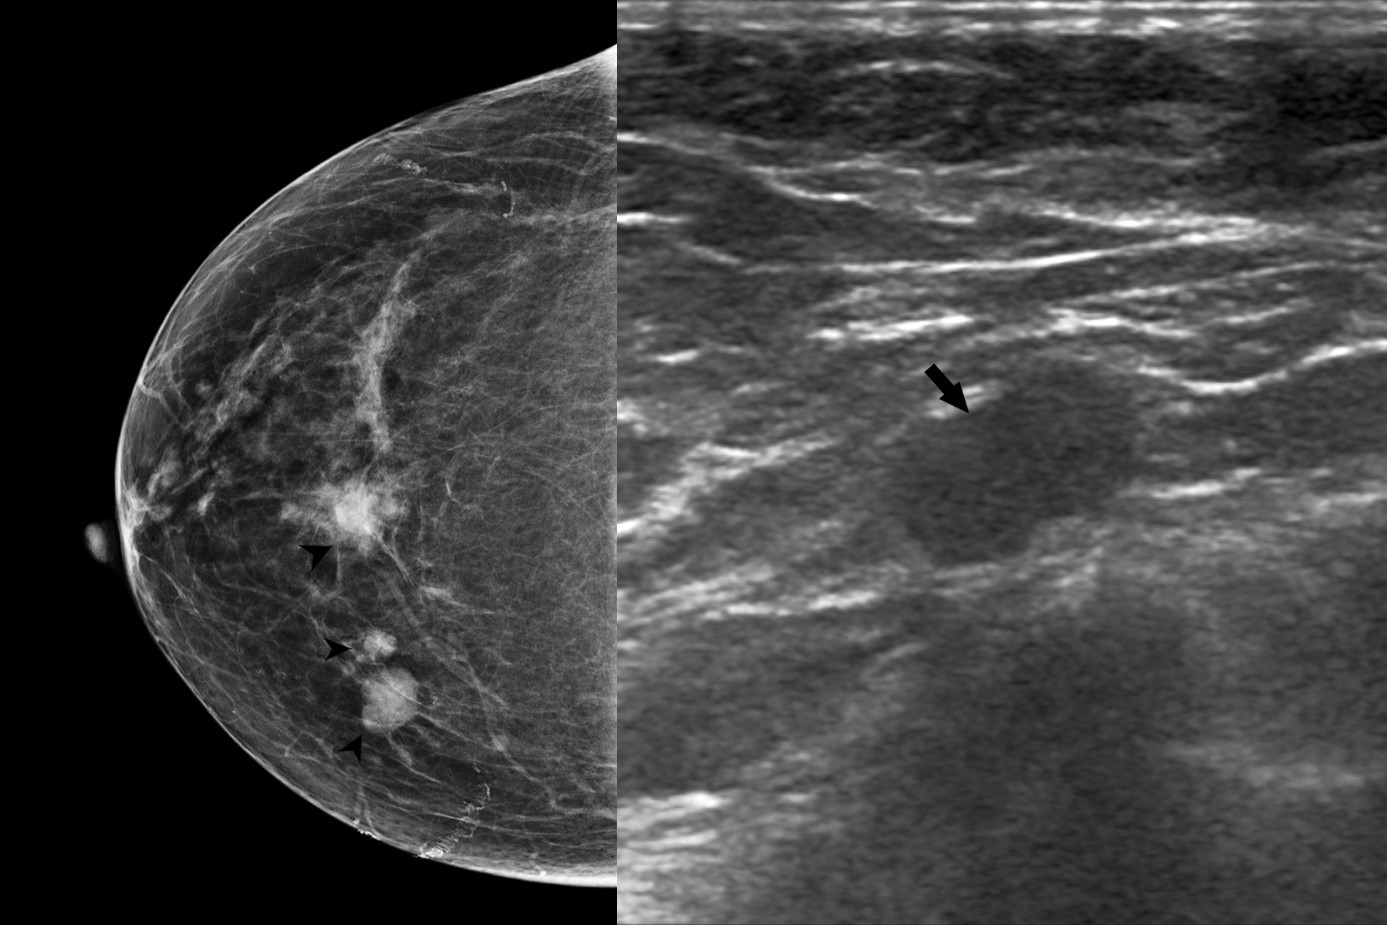

Findings Extremity X rays taken at the time of presentation to revealed lytic lesions in the metatarsal and the calcaneum. Subsequently she underwent a PET CT which revealed multifocal right breast lesions in the upper inner quadrant (White arrow heads) with right internal mammary node (white arrow) and sternal lesion (white star ).Bilateral axillary nodal uptake(solid black arrows)was seen along with multiple other lytic bony lesions (block black arrows ) Pre -biopsy Right mammogram (RCC) showed a larger spiculated and smaller irregular masses in the upper inner quadrant (Black arrow heads) .Axillary nodes showed diffuse cortical thickening on USG (black arrow),which were concerning for metastasis.Core biopsy specimen stained with H&E (x 400) demonstrated diffuse dense infiltration by lymphocytes, plasma cells and histiocytes. Emperipolesis- meaning phagocytosis of lymphocytes by histiocytes (Black arrow head) was seen in the samples.Immunohistochemistry revealed histiocytes demonstrating positivity for S100(x 400)